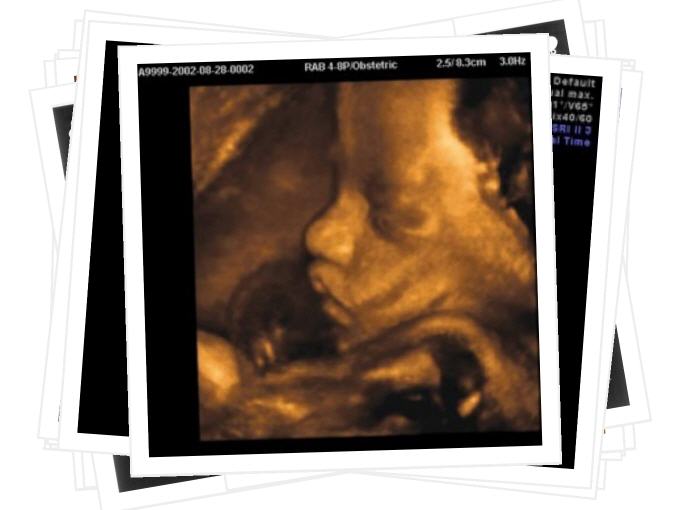

Geburtshilfe

Auf den folgenden Seiten können Sie sich einen Überblick über unser umfassendes Leistungsspektrum im Bereich Geburtshilfen und Pränataldiagnostik verschaffen.